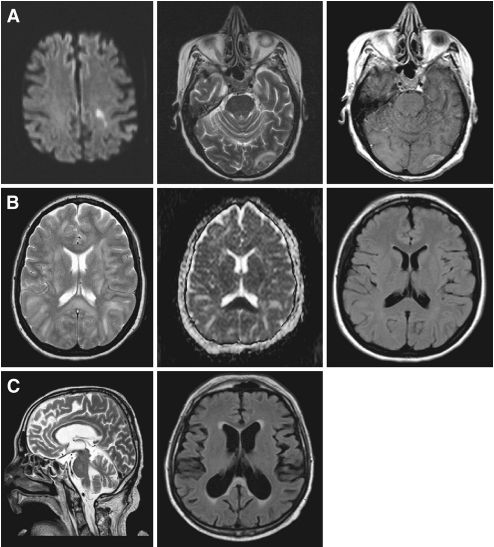

结果发现,27例(29%)SIBD患者颅脑MRI扫描无异常发现,51例(54.9%)显示脑组织病理学损伤,15例(16.1%)脑萎缩(图1)。VBM分析显示,岛叶、扣带皮层、额叶、楔前叶和丘脑神经元丢失(图2)。MRI检查结果异常的患者APACHE Ⅱ、SOFA、GOSE评分较差,谵妄发生率和死亡率高。MRI发生病变与C5a和iC3b水平降低相关,脑萎缩与p-tau水平升高有关。

图1. SIBD患者典型的MRI表现。A.谵妄性脓毒性休克患者的急性缺血表现;在脓毒性休克发作后第6天进行MRI检查,DWI、T2和T1加权增强图像显示大脑左半球深部和皮质分水区的急性缺血引起的弥散受限和高信号。B.26岁的脓毒性休克患者出现可逆性白质脑病综合征(PRES),有局灶性神经系统体征;MRI-T2加权和ADC成像显示,与PRES一致的脑深部白质和胼胝体中的高信号和弥散受限。C.58岁男性患有严重急性呼吸窘迫综合征,MRI 轴向FLAIR和矢状T2加权图像显示,轻度脑萎缩和脑室扩大。